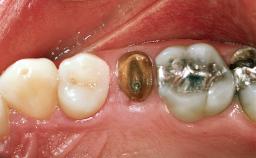

In June 2002, a healthy and cooperative 42-year-old female patient was referred for consultation and for the treatment of a fractured maxillary left second premolar. The patient reported an uncomplicated medical history, significant only for seasonal allergies. She had been in the continuous care of a general dental practitioner at the University of Florida College of Dentistry for more than ten years, her recent dental history being restricted to routine operative dentistry and periodontal maintenance. Her plaque control and gingival health was considered for the most part to be excellent, and no intraoral periodontal probing depths exceeded 3 mm. Her esthetic demands were considered moderate to high, and she displayed a high smile line. Intraoral examination revealed a Class I malocclusion, characterized by minor tooth misalignment and midline disharmony, for which orthodontic therapy was recommended and rejected. Her gingival biotype was considered medium to thick.